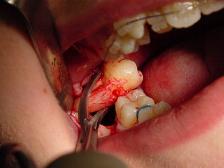

Surgical extractions involve the removal of teeth that cannot be easily accessed or removed via simple extraction, for example because they have broken under the gum or because they have not erupted fully, such as an impacted wisdom tooth.[1] Surgical extractions almost always require an incision. In a surgical extraction the dentist may elevate the soft tissues covering the tooth and bone, and may also remove some of the overlying and/or surrounding jaw bone with a drill or, less commonly, an instrument called an osteotome. Frequently, the tooth may be split into multiple pieces to facilitate its removal.

العملية الجراحية

- Incisions are made full thickness through mucosa and periosteum to bone. In general, the flap is extended from one tooth behind the tooth concerned to one tooth in front, including the interdental papilla.

- An anterior relieving incision is made extending down into the sulcus. This flap design is called “two sided”. A “three sided” flap includes an additional relieving incision posteriorly.

- The flap is raised using periosteal elevator to expose the area of interest.

- The flap is held out of the way with an instrument such as a rake retractor.

- A small gutter of bone is drilled away around the tooth to make space into which an application point for instruments can be achieved. It is important that copious amount of saline is used to cool the bone during this process.

- The tooth concerned can be removed using a combination of luxators, elevators and extraction forceps.

- Any sharp bone is smoothed off and the wound is irrigated with saline.

- The flap is repositioned and sutured in place.[1]